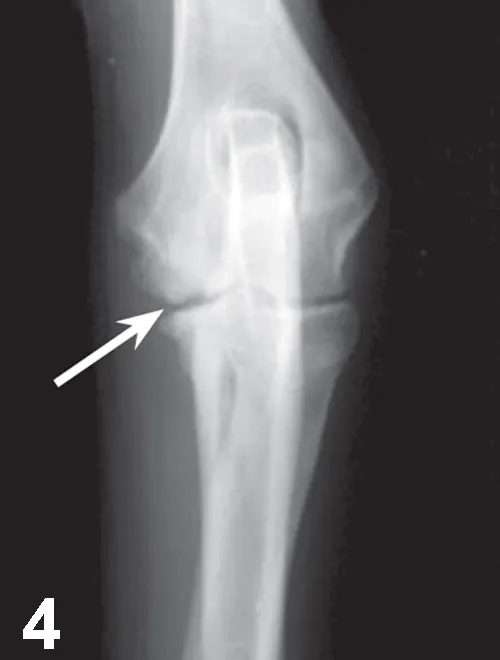

Elbow dysplasia is an umbrella term for several conditions (eg, ununited anconeal process [UAP], medial coronoid disease [MCD], osteochondrosis [OC]/OCD, incongruency) resulting in OA. Most patients are affected by only 1 or 2 of these conditions at the same time (eg, fragmented medial coronoid process, humeral OCD). The causes are multifactorial; genetic and environmental factors are involved. Dogs present with unilateral or bilateral lameness or stiffness of the forelimbs with effusion, pain, and decreased range of motion of the elbow. In dogs older than 5 months of age, radiographs of the joint may show a radiolucent line in the anconeal process (ie, UAP; Figure 3), an articular defect in the medial aspect of the humeral condyle (ie, OC, OCD; Figure 4), sclerosis and blunting of the medial coronoid process (ie, MCD), degenerative changes, or joint incongruency.

Figure 3.

Mediolateral radiograph of the elbow in a 7-month-old German shepherd dog with joint effusion and pain of the elbow. A radiolucent line (arrow) can be observed between the anconeal process and proximal ulna, consistent with UAP.